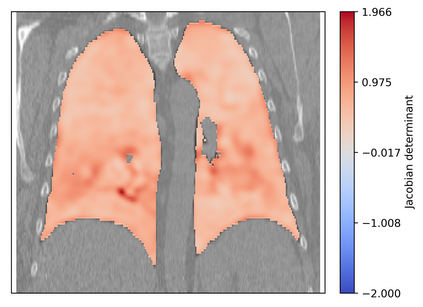

Deformable image registration is a fundamental task in medical image analysis and plays a crucial role in a wide range of clinical applications. Recently, deep learning-based approaches have been widely studied for deformable medical image registration and achieved promising results. However, existing deep learning image registration techniques do not theoretically guarantee topology-preserving transformations. This is a key property to preserve anatomical structures and achieve plausible transformations that can be used in real clinical settings. We propose a novel framework for deformable image registration. Firstly, we introduce a novel regulariser based on conformal-invariant properties in a nonlinear elasticity setting. Our regulariser enforces the deformation field to be smooth, invertible and orientation-preserving. More importantly, we strictly guarantee topology preservation yielding to a clinical meaningful registration. Secondly, we boost the performance of our regulariser through coordinate MLPs, where one can view the to-be-registered images as continuously differentiable entities. We demonstrate, through numerical and visual experiments, that our framework is able to outperform current techniques for image registration.